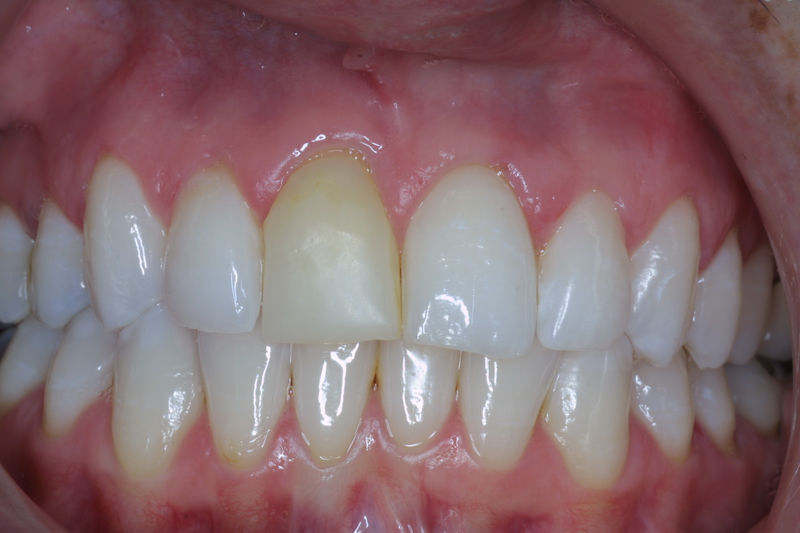

Cirugía ortognática, implantes, carillas y coronas,